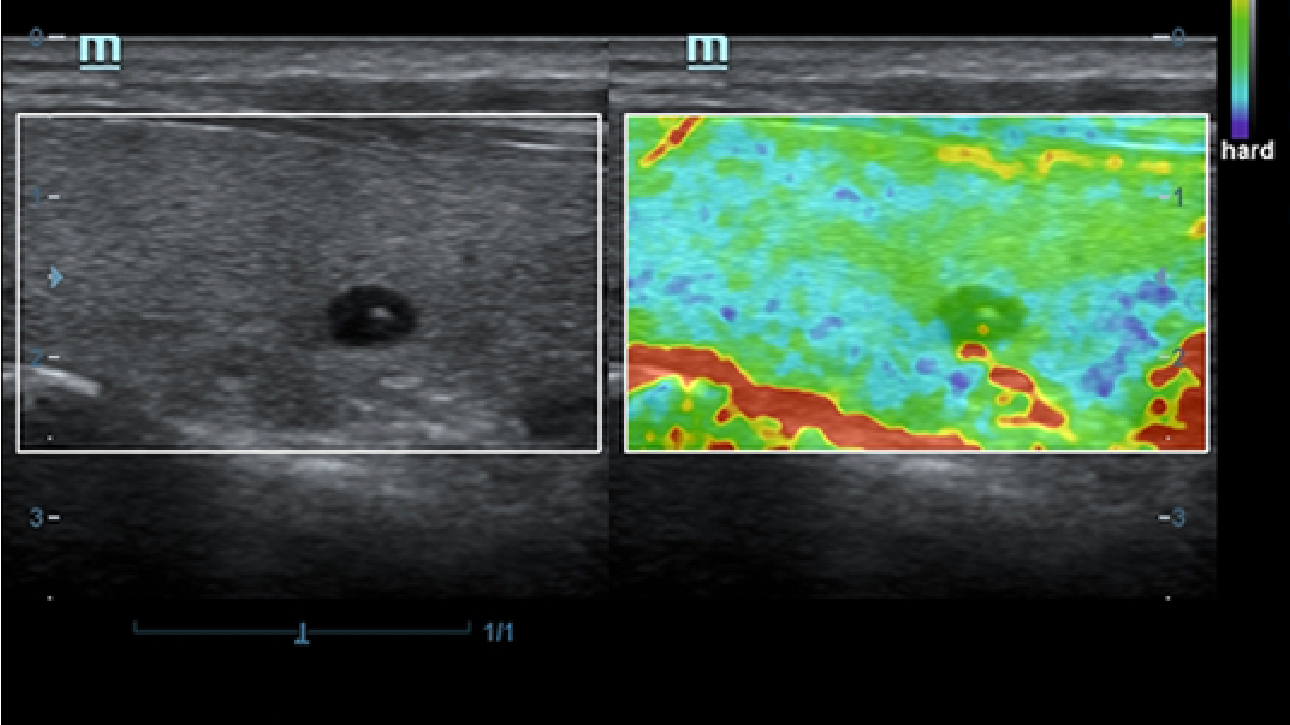

X-Insight is een inzichtelijke oplossing om meer visie te krijgen.

De gloednieuwe oplossing van Mindray is het geslaagde product dat is voortgekomen uit voortdurende klantinzichten in klinische behoeften in combinatie met steeds evoluerende, geavanceerde ultrasoundtechnologie?n. Vol energie en gebrand op toekomstgerichte inzichten en eindeloze mogelijkheden: dankzij de verhoogde schaalbaarheid wordt de oplossing continu verbeterd.

Als allround partner zet DC-60 Exp met X-Insight zich in om een allesomvattende oplossing te zoeken waarmee u alle aspecten van uw dagelijkse klinische activiteiten gemakkelijk en trefzeker kunt beheren.

De DC-60 Exp met X-Insight is ontworpen op basis van diepgaand inzicht in klantbehoeften om hoge effici?ntie met nauwkeurige beeldverwerking te leveren, dankzij eXacte helderheid, eXceptionele intelligentie en eXcellente ervaring.